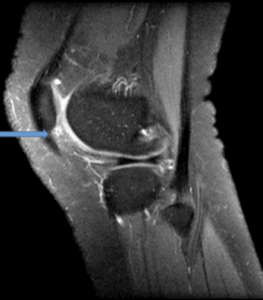

Figure 8b: 17 year old coronal (PD/FS) demonstrates tear of the patella insertion of the medial patellofemoral ligament complex (blue arrow). Small minimally displaced osseous fragment along the inferior medial patella (green arrow).

Figure 9a: 15 year old patient with patella maltracking and a history of recurrent patella subluxation. The patient has trochlear dysplasia (green arrow). There is majority chondral surface delamination of along the medial patella facet (grade III, blue arrow, axial view, PD/FS).